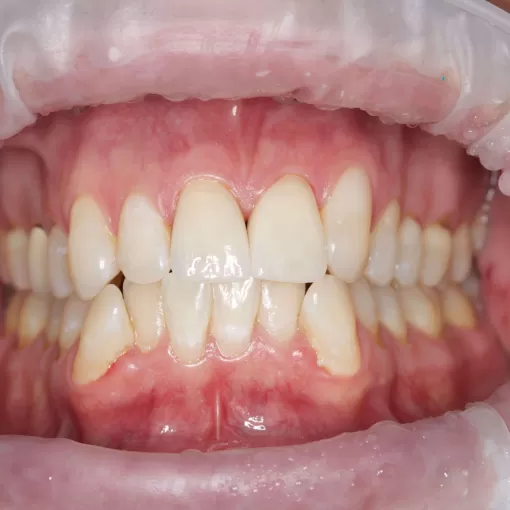

Пациентка обратилась к нам за эстетикой и для подготовки к ортопедическому лечению

Стоматолог-ортодонт Парейко П.А.

Стоматолог-хирург-имплантолог Патеюк А.Л.

Пациентка обратилась к нам за эстетикой и для подготовки к ортопедическому лечению. В ходе диагностики было выявлено: адентия зуба 2.5, аномальной формы (шиповидный) зуб 1.5, глубокое резцовое перекрытие, давнее удаление зуба 4.6 и, как следствие, вторичная деформация зубных рядов.